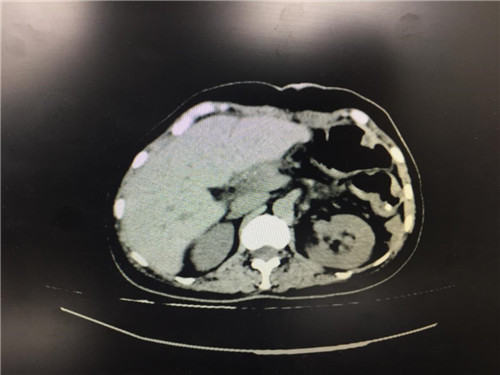

2月12日,普外科收治了一名女性患者,该患者入院一个月前,无明显诱因出现上腹部疼痛不适,呈间断性,向腰背部放射,有恶心,无呕吐,近一个月体重下降了5kg。门诊查上腹部CT提示:胰颈部新生物并胰管扩张;副脾。

患者病情复杂,在潘承恩教授和全科医生的讨论下,结合检验及检查结果,术前胰腺颈体部肿瘤诊断明确,科室积极制定手术方案,详细向家属探明病情并取得合作。2月21日,由普外科史和平主任、梁鹏锋医师主刀,在王谦、李垚磊医师配合下,成功对该患者实施了剖腹探查、全胰腺切除、脾脏切除术。手术中发现,患者胰腺颈体部可触及一大小约4cm包块,胰头部质软,胰腺体尾部质硬,遂决定行胰腺颈体尾部切除及脾脏切除术。在胰腺近侧断端切取部分胰腺组织送术中快速冰冻,提示查见异型增生的胰腺腺泡样组织,联系病理科考虑癌细胞残留,术中向家属谈明病情并取得同意,遂行胰十二指肠切除术,手术顺利,术后生命体征平稳,并于术后第四日进行了复查CT结果良好。